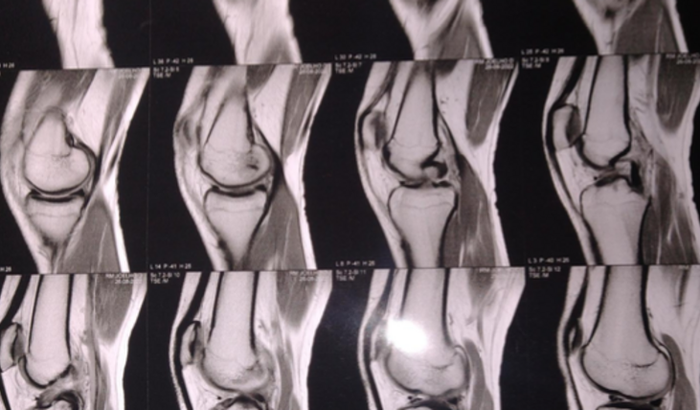

Segundo o escritor Fernando Pessoa: matar o sonho é matarmo-nos. É mutilar a nossa alma. O sonho é o que temos de realmente nosso, de impenetravelmente e inexpugnavelmente nosso. Assim, inspiradas pela frase desse grande escritor venho pedir encaredecidamente ajuda . Priscila, assim como todos nós, tem um sonho: ser jogadora de futebol. Mas, infelizmente o seu sonho, que já possui muitos empecilhos, foi interrompido por uma fatalidade, Priscila rompeu o ligamento do joelho, fazendo o que ela mais gosta que é jogar futebol. A fila de espera no sus é de mínimo 2 anos e ela não tem todo esse tempo, já que a carreira do futebol exige alto desempenho, que requer muito treino. Sua alternativa é fazer uma cirurgia em hospital privado, no valor de R$16000. No entanto, sua família não possui condições para arcar com esses custos. Peço então a sua ajuda para que o sonho de Priscila não morra. Qualquer ajuda é bem vinda, todo valor será de grande ajuda e sua contribuição será responsável por um sonho.Pix: (11)946156217Lembre-se: nada é tão nosso quanto nossos sonhos.